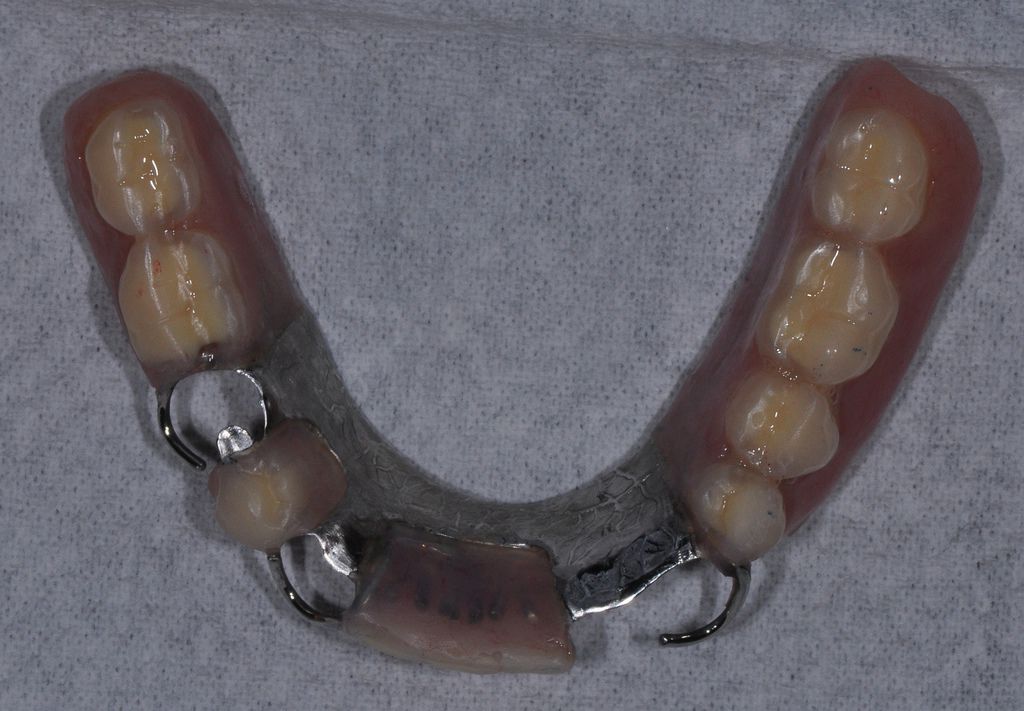

一個功能正常設計良好的

活動假牙,會透過一些假牙上的設計,或零件與嘴巴裡剩下的牙齒或植牙來固定,最常見的方式就是鉤子。透過這些方式來固定後,使用活動假牙來吃東西時在口內是穩定狀態,但是在休息或清潔的時候,病人可以將活動假牙自己從嘴巴取下來做清潔的動作,所以活動假牙不是吃東西的時候會動來動去,而是指病人可以在需要的時候自由取下。